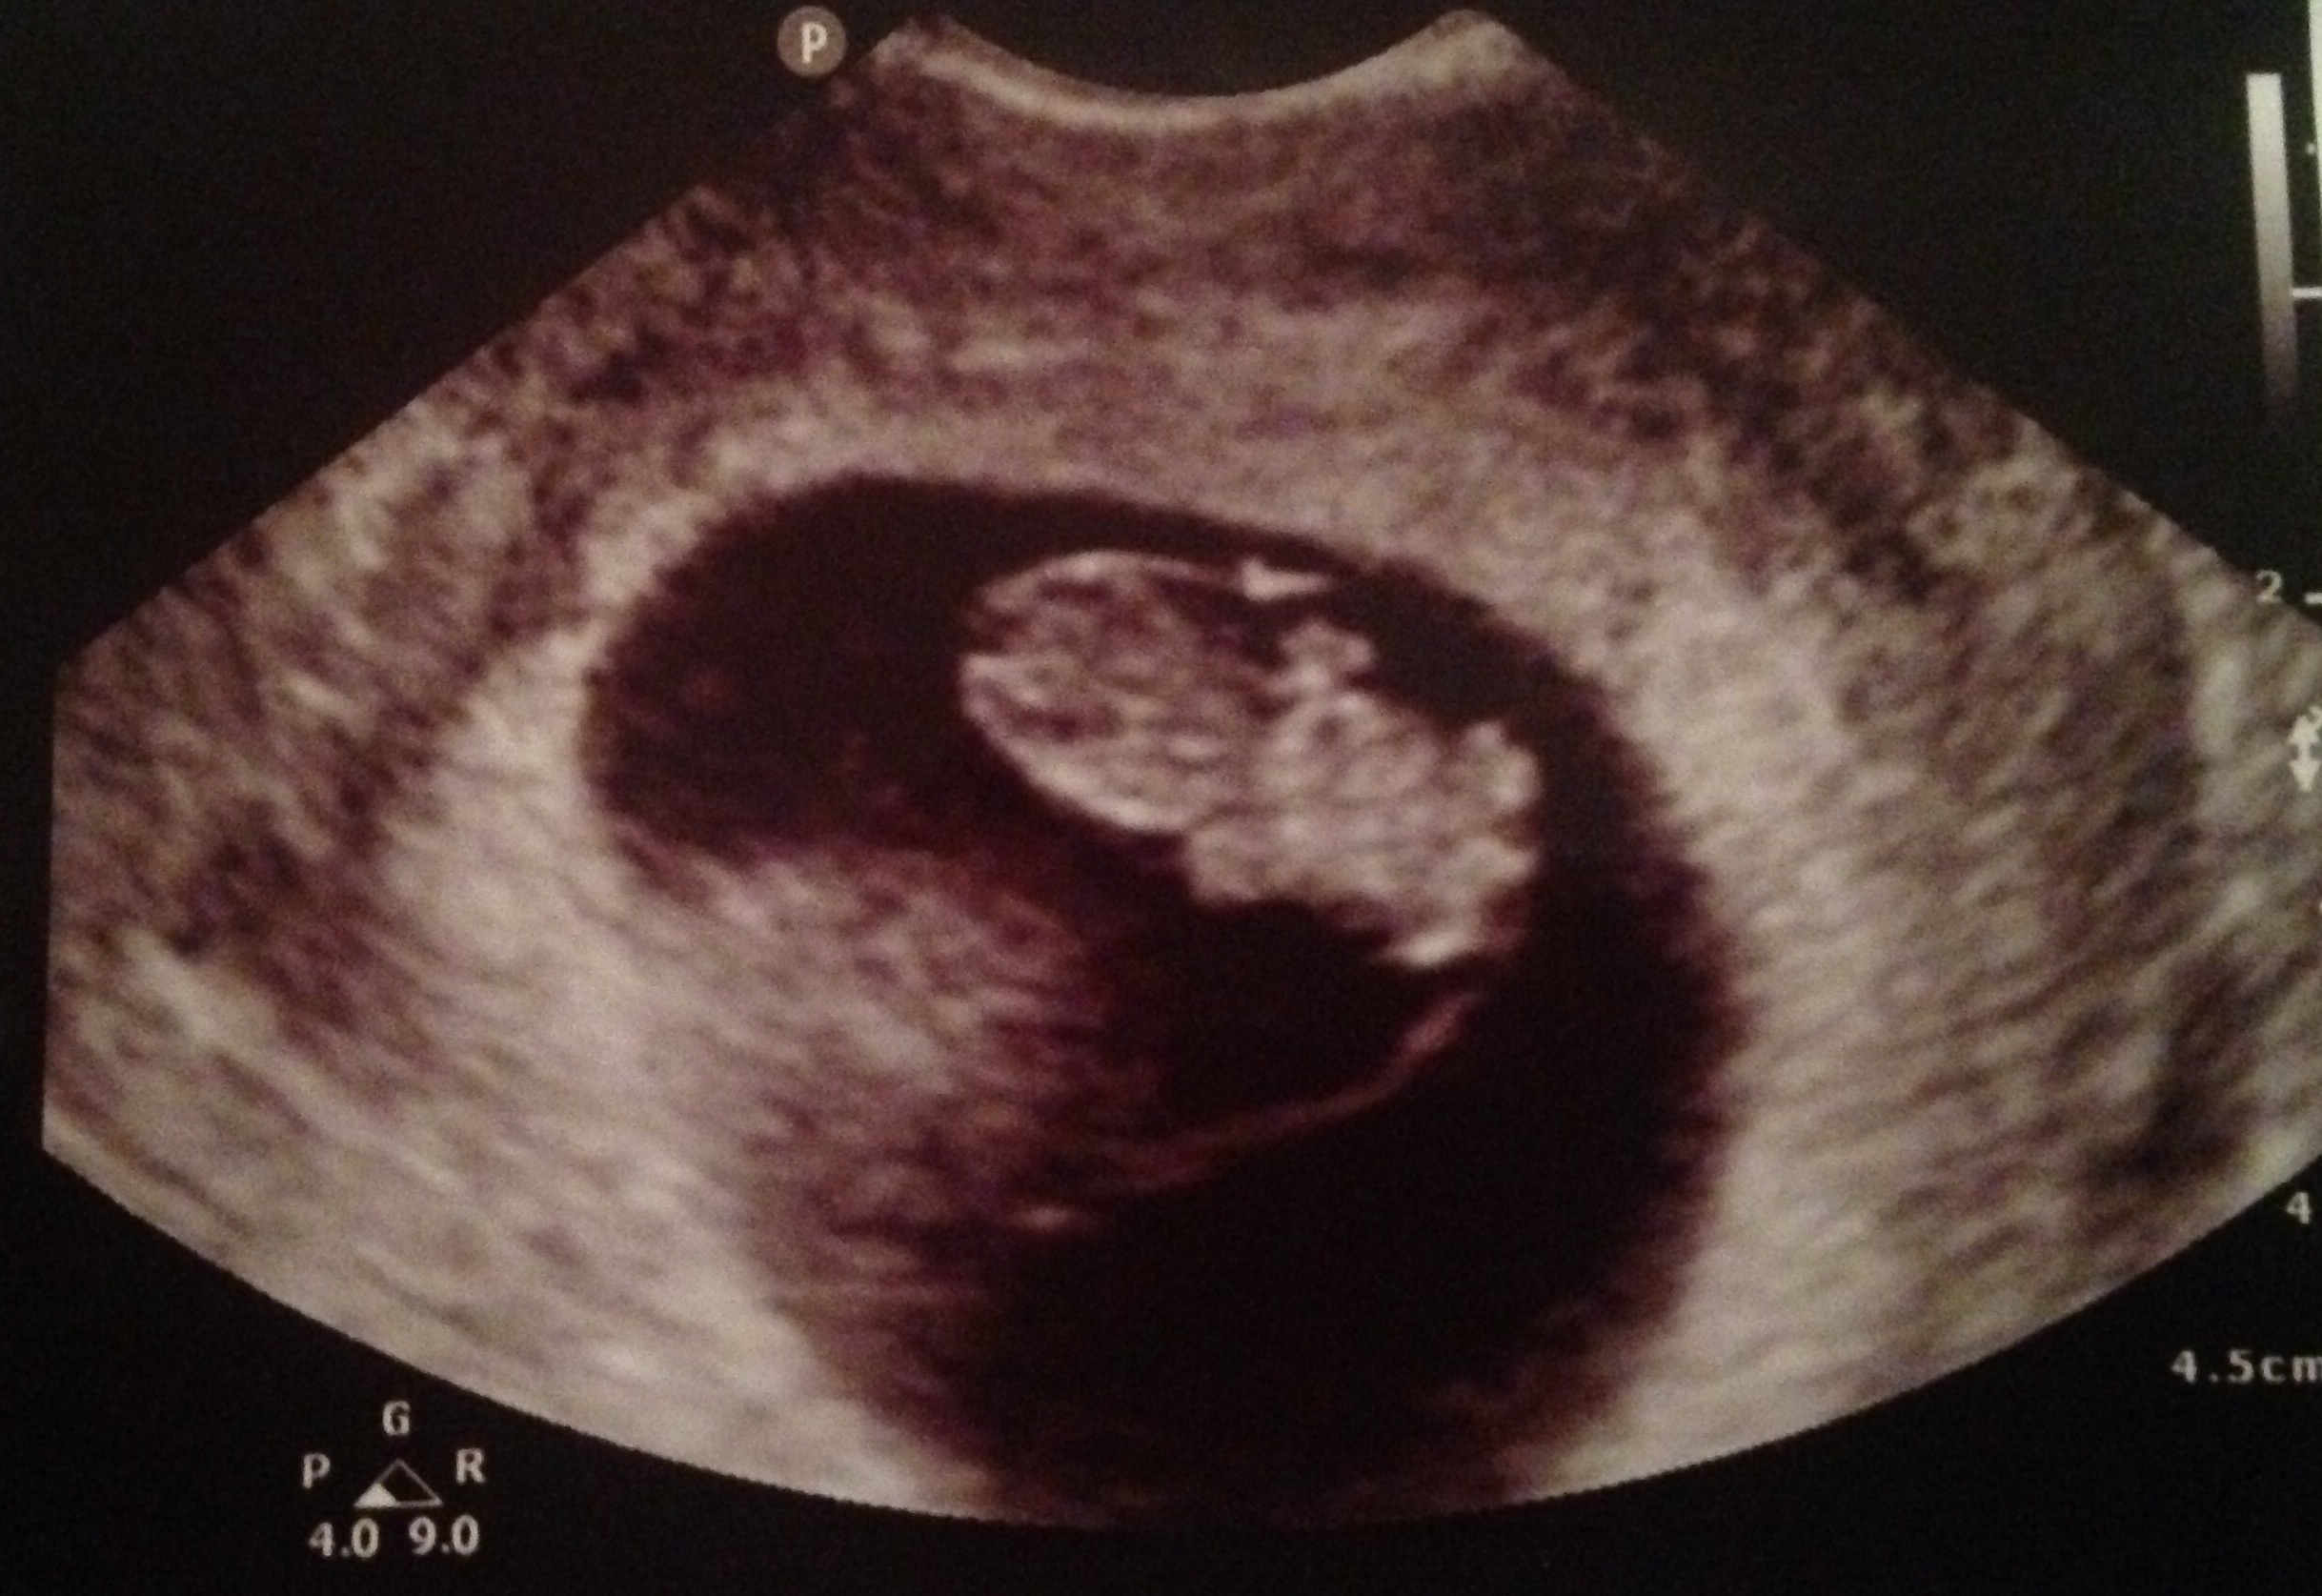

This is my transvaginal ultrasound. Baby is in the middle but you can see placenta forming on the left which indicates a girl. Still don't know if it's accurate